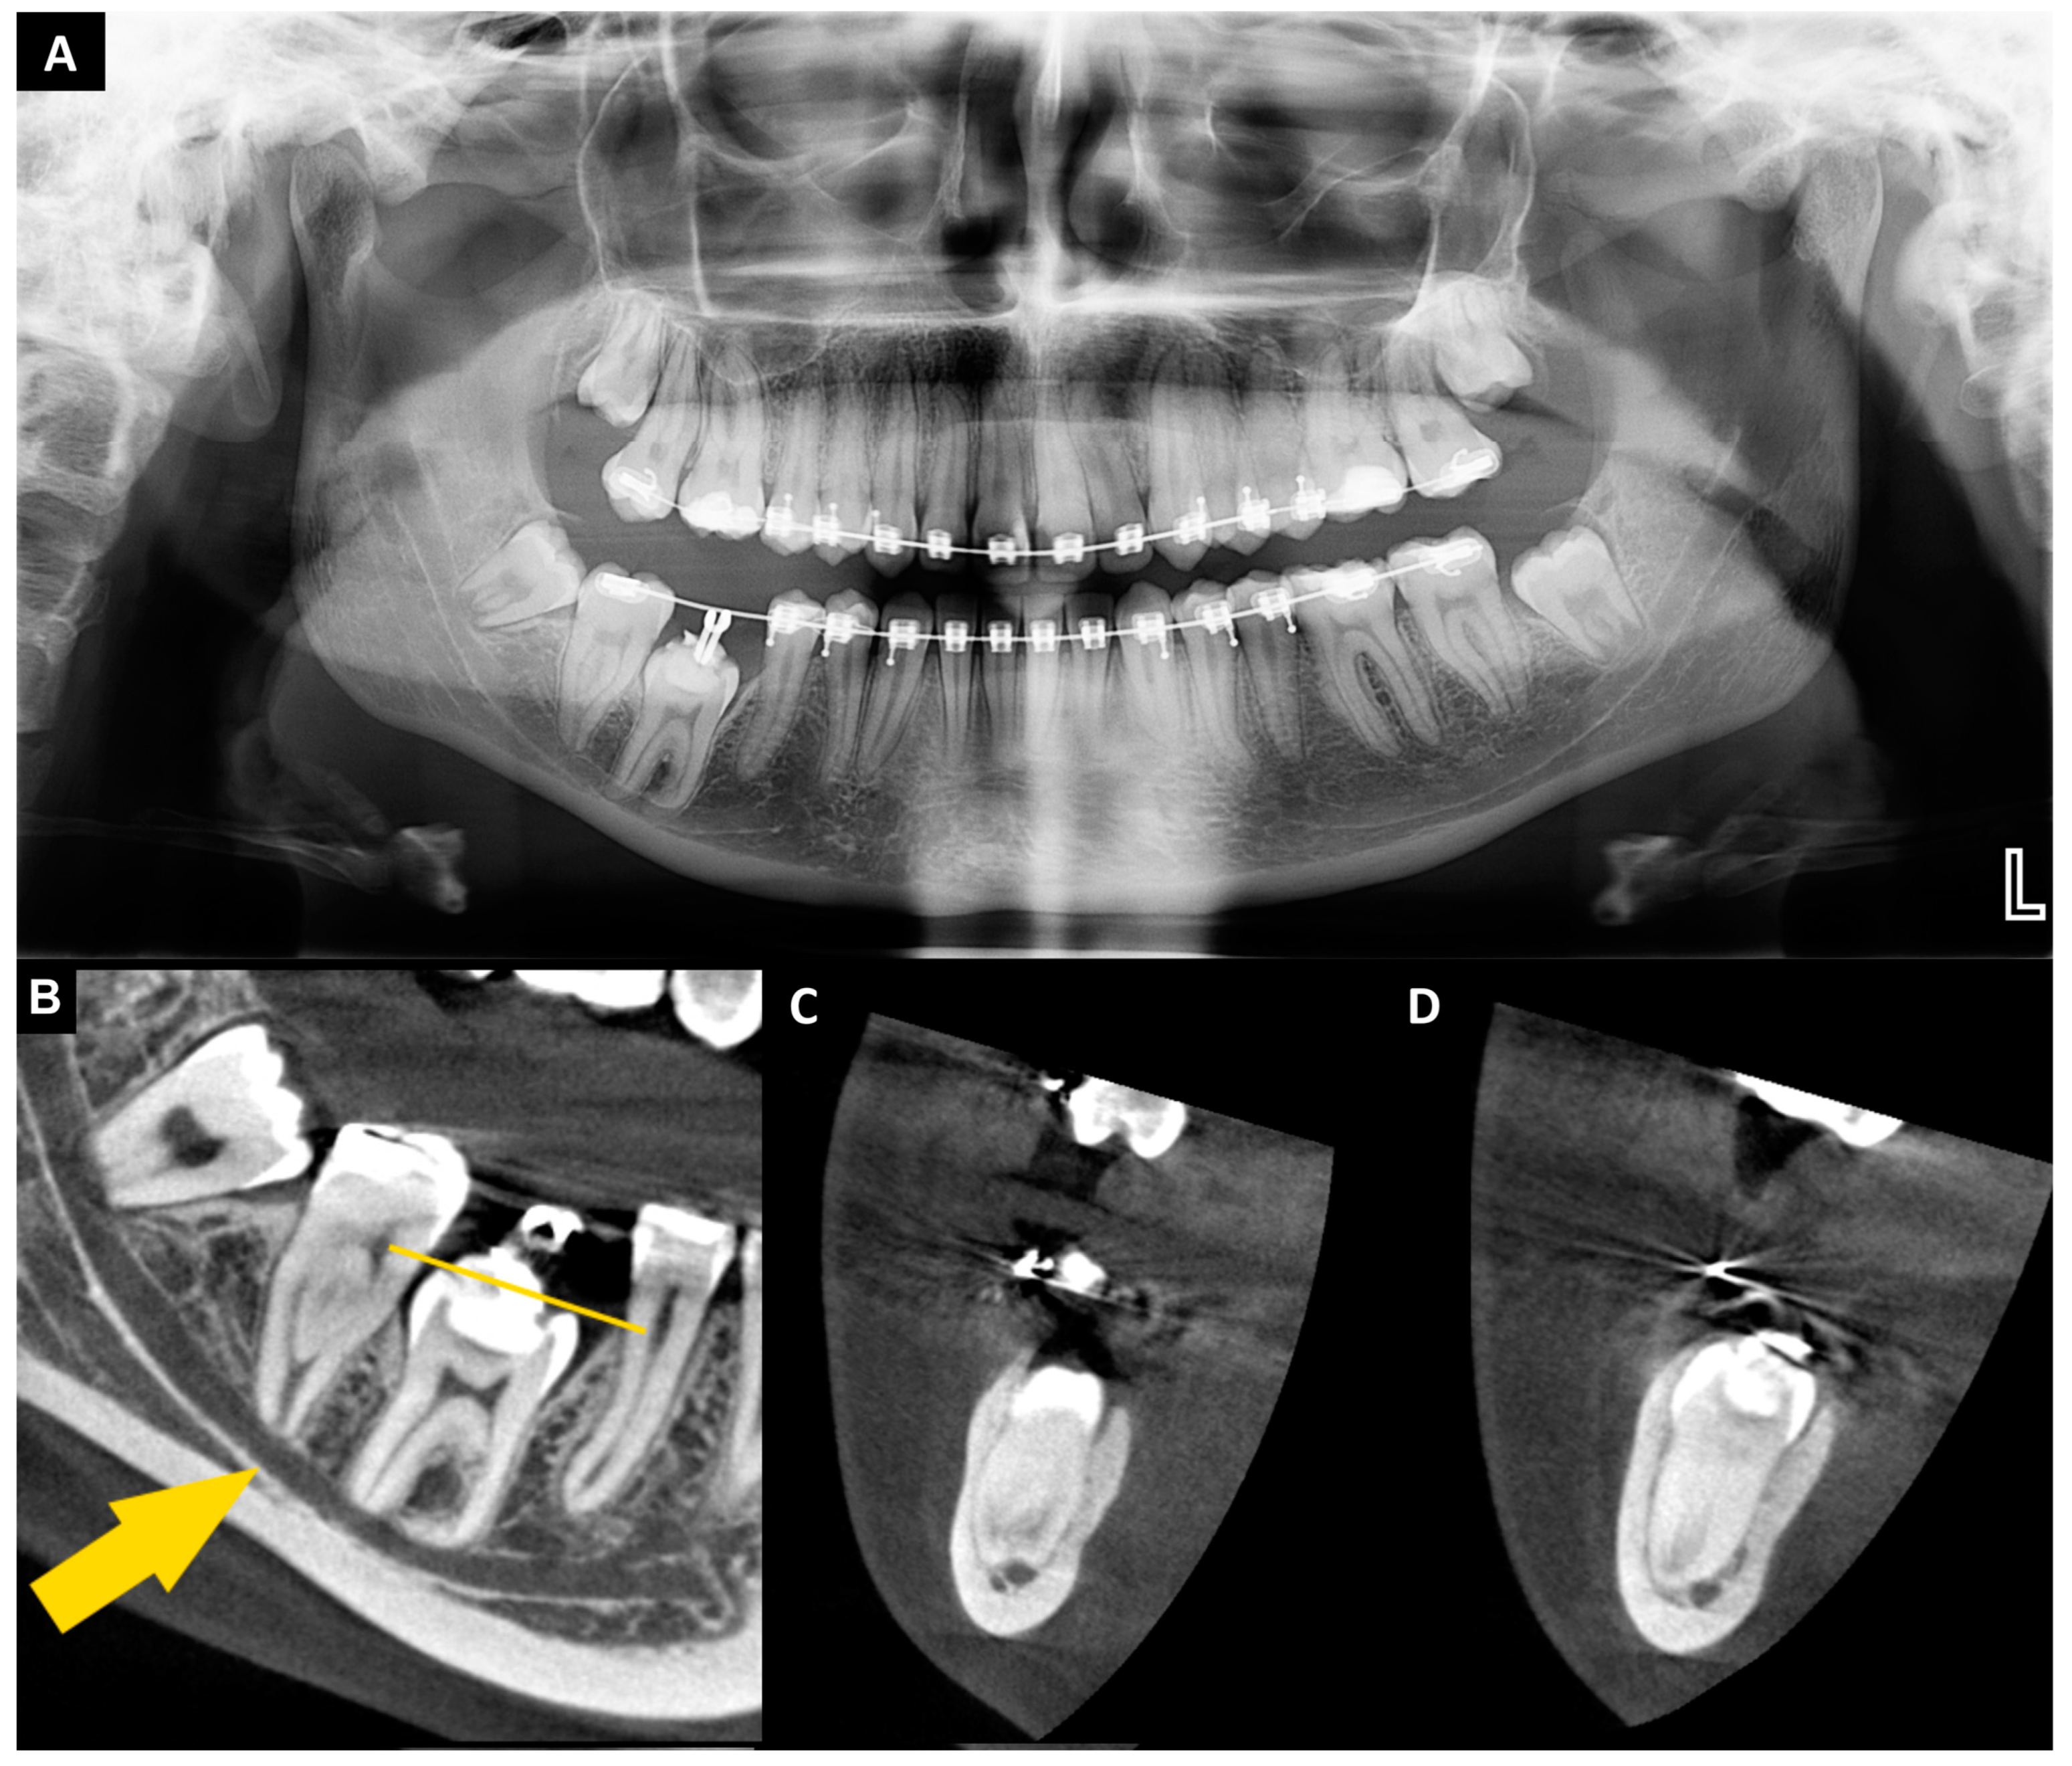

The patient was generally healthy, with no systemic diseases or allergies, did not take any medications, was a non-smoker, and had good oral hygiene. Extraoral and intraoral examinations, orthopantomography, and cone beam computed tomography (CBCT) were performed (Figure 1A–D). The CBCT was assessed using CS 3D Imaging v3.5.18 software (Carestream Health Inc., Trophy, Croissy-Beaubourg, France). The imaging conditions were 84 kV, 5 mA, with a voxel size of 0.1 mm, a field of view (FOV) of 6×6 cm, and CTDIvol 2.66 mGy. The CBCT examination revealed that tooth no. 46 was located under the mucous membrane while maintaining contact with the oral environment through a narrow canal lined with epithelium. This tooth was classified as a severe type of reinclusion. The mesial root was dilacerated and both of the roots were in close position to the inferior alveolar nerve canal. Removing this tooth was associated with a high risk of nerve damage and neurosensory disturbances. Due to the presence of severe infraocclusion of tooth no. 46, the surgical procedure was planned as follows (after 2 years of unsuccessful orthodontic treatment, without prior surgical support): the extraction of tooth no. 46, grinding the tooth no. 46 to obtain a dentin graft, adding A-PRF clots (collected from the patient’s peripheral blood) to the autogenous dentin graft, creating the A-PRF membrane, and atraumatic extraction and transplantation of tooth no. 38 (lower left third molar). The alveolar socket after the removal of tooth no. 46 did not require additional preparation due to the larger size of tooth no. 46 compared to tooth no. 38. Stabilization of tooth no. 38 was performed with an orthodontic bracket splint, and a bone graft was put in place of tooth no. 46. The patient signed an informed written consent for the procedures and the use of the data and photos for publication.

Figure 1.

Orthopantomography (A) reincluded tooth no. 46 and donor—tooth no. 38; cone beam computed tomography (B–D) (radiological examinations performed 1 month before the procedure): (B) sagittal view—severe reinclusion of tooth no. 46 (yellow line—the crown of the tooth located under the mucous membrane); yellow arrow—inferior alveolar nerve canal); (C) cross-sectional view—mesial root of tooth no. 46 in relation to IANC; (D) cross-sectional view—distal root of tooth no. 46 in relation to IANC.